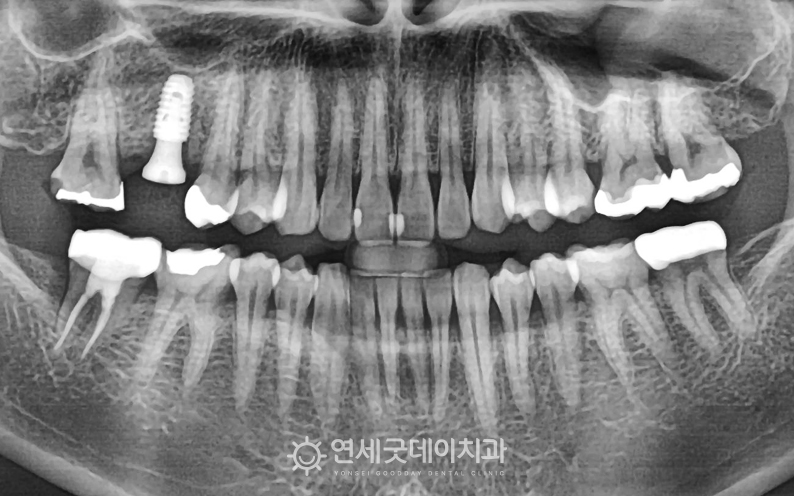

환자분은 당일에 잇몸뼈이식과 임플란트 식립을 병행하며

▲ 치료 중 X-Ray (촬영시기 : 2023년 10월)

골이식재와 픽스쳐가 잘 심어졌으며,

▲ 어금니 임플란트 치료종결 (촬영시기 : 2024년 5월)

골이식재와 임플란트가 성공적으로 융화되며

지르코니아 보철물로 마무리하며